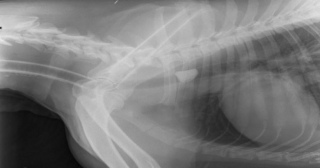

Pour retirer le caillou qui faisait suffoquer Rocky, il était crucial de faire preuve de précision. Victoria a donc utilisé une caméra pour localiser le corps étranger, lequel était coincé dans une bronche du toutou, c’est-à-dire dans le tube menant à son poumon. S’il n’était pas retiré rapidement, Rocky risquait de développer des complications respiratoires plus sévères.

© Anderson Moores Veterinary Specialists